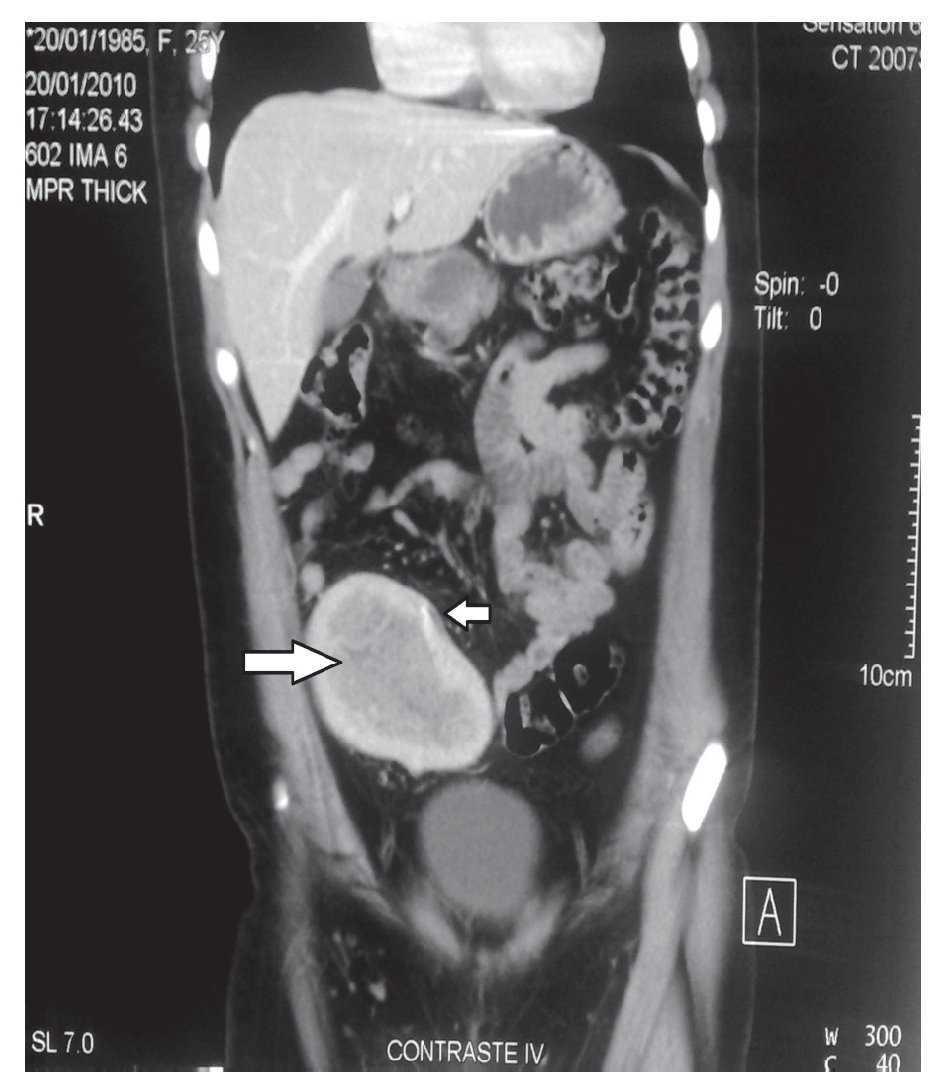

WebEl dolor abdominal constituye casi el 85% de las asistencias en los servicios de urgencias, sobre todo si aparece bruscamente. Dolor abdominal agudo = dolor de menos de 24. WebLas fosas iliacas. son dos cavidades óseas situadas en la parte inferior del abdomen, a ambos lados de la línea media del cuerpo. Estas fosas están formadas por los huesos. WebMujer de 21 años, sin alergias medicamentosas ni antecedentes de interés, nuligesta, remitida desde atención primaria por dolor abdominal brusco de hora y media de.

WebLa fosa del ilion puede presentar dolor de manera directa, principalmente por la instauración de procesos degenerativos, como es el caso de la osteoartrosis, pero debido a que. WebLa presencia de dolor en la fosa ilíaca derecha puede ser signo de algún problema sanitario, como puede ser la apendicitis. De todos modos, al igual que ocurre con la. Webfosa iliaca derecha en mujeres de 15 a 30 aÑos de edad estudio a realizarse en el hospital general martin icaza desde 1 de enero hasta el 31 de diciembre 2015 trabajo de. WebCausas del dolor de la cresta ilíaca. Músculos débiles. Si los músculos del abdomen y de la espalda inferior son demasiado débiles, la cresta ilíaca se puede ver afectada,. WebEl dolor abdominal agudo localizado en la fosa ilíaca derecha (FID) es uno de los principales motivos de consulta por dolor tras el traumático en las urgencias. WebMujer de 21 años, sin alergias medicamentosas ni antecedentes de interés, nuligesta, remitida desde atención primaria por dolor abdominal brusco de hora y media de. WebIntroducción. El dolor agudo en fosa ilíaca derecha (dFID) representa un problema diagnóstico, ya que puede englobar diferentes causas, y a veces es difícil tomar una. Webmedia y profunda en la fosa iliaca derecha, con signos de McBurney, Rovsing, Lanz, Capurro, Psoas, Obturador, Von Blumberg y talopercusión positivos; perístasis.

Webcon presencia de dolor abdominal tipo cólico, 8/10 EVA, en fosa iliaca derecha, sin irradiaciones ni exacerbaciones, el cual se acompañaba de náusea, llegando en 2. WebIntroducción. El dolor en la fosa ilíaca izquierda (FII) es un motivo de consulta muy frecuente en la práctica clínica habitual, suponiendo un reto diagnóstico. En su origen, podemos. WebDolor en fosa iliaca derecha, con migración previa, asociado a signos de respuesta inflamatoria como fiebre y desviación izquierda, por lo que se trata de un cuadro.